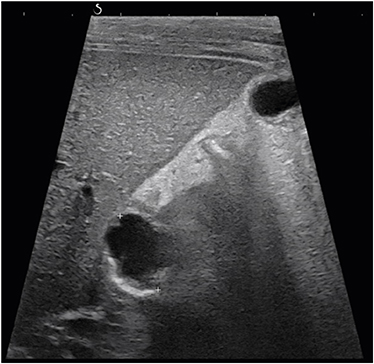

After admission, a follow-up MRCP (Fig. 1) and ultrasonography (Fig. 2) revealed a 1.7 cm-sized cystic lesion around the CBD and duodenum showing no definite communication with the CBD, indicative of a duodenal duplication cyst causing biliary obstruction or an unusual choledochal cyst or choledochocele. To evaluate the relationship between the cystic lesion and the duodenum, a upper gastrointestinal series and computed tomography were taken and showed mild narrowing at the proximal duodenum with no evidence of communication between the cyst and the duodenum. However, the structural continuity between the cyst and the biliary tree still remained unclear, so a percutaneous transhepatic cholangiography (Fig. 3) was performed and revealed a cystic lesion located at the confluence level between the common hepatic duct (CHD) and cystic duct (CD) with possible communication with the CD, highly suggestive of Todani type II choledochal cyst.

Fig. 2

Ultrasonography showing 1.7 cm-sized cystic lesion.